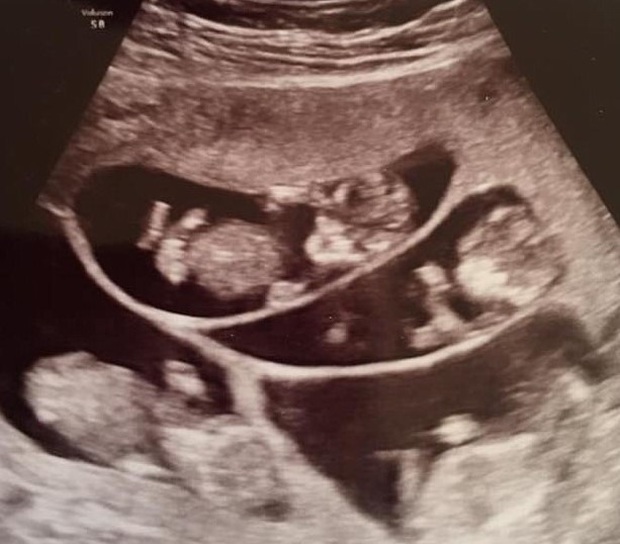

khoẻ cho cả hai mẹ con. Rồi ngày định mệnh ấy cũng đến, hôm đó, cặp đôi

có mặt để siêu âm như thường lệ thì bác sĩ thông báo trong bụng Bobbi

không phải có một phôi thai mà có tận… 7 cái.